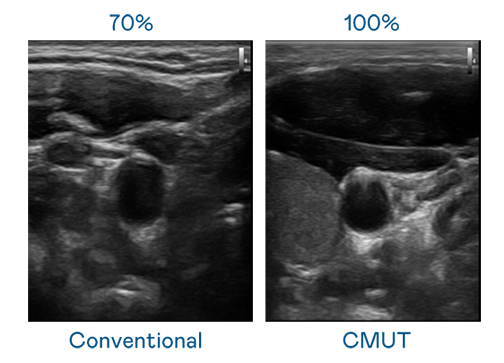

CMUT 技术是一种用电容式微机电元件来产生超音波讯号的技术。与传统 PZT 压电式技术相比,CMUT 频宽增加 30%,更宽频的超音波讯号让影像解析度大幅提升,是实现高影像品质医疗超音波扫描、促进精准医疗发展的关键技术。

超音波影像的解析度高低,首先取决于探头能发出的讯号频宽。4001百老汇 CMUT 可提供高清晰的超音波讯号,提供高频宽、高灵敏度、影像纹理细节更高的超音波影像,协助医护人员缩短影像判读时间及利用精准的医疗影像进行诊断。